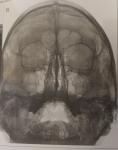

Пневмония, гайморит

Здравствуйте, у сына подозрение на пневмонию и гайморит. Температурил(39,6 по вечерам, пропили антибиотики, назначенные врачом, другие лекарства), спала до 36,9, затем опять стала подниматься. Немного кашляет. Не могли бы Вы посмотреть снимки, помочь с постановкой диагноза? Заранее благодарю Вас.

Гайморита нет. Двусторонний ринит.

Пневмонии тоже не вижу, лишь немного усиления легочного рисунка справа внизу. Но такое бывает и при бронхите.